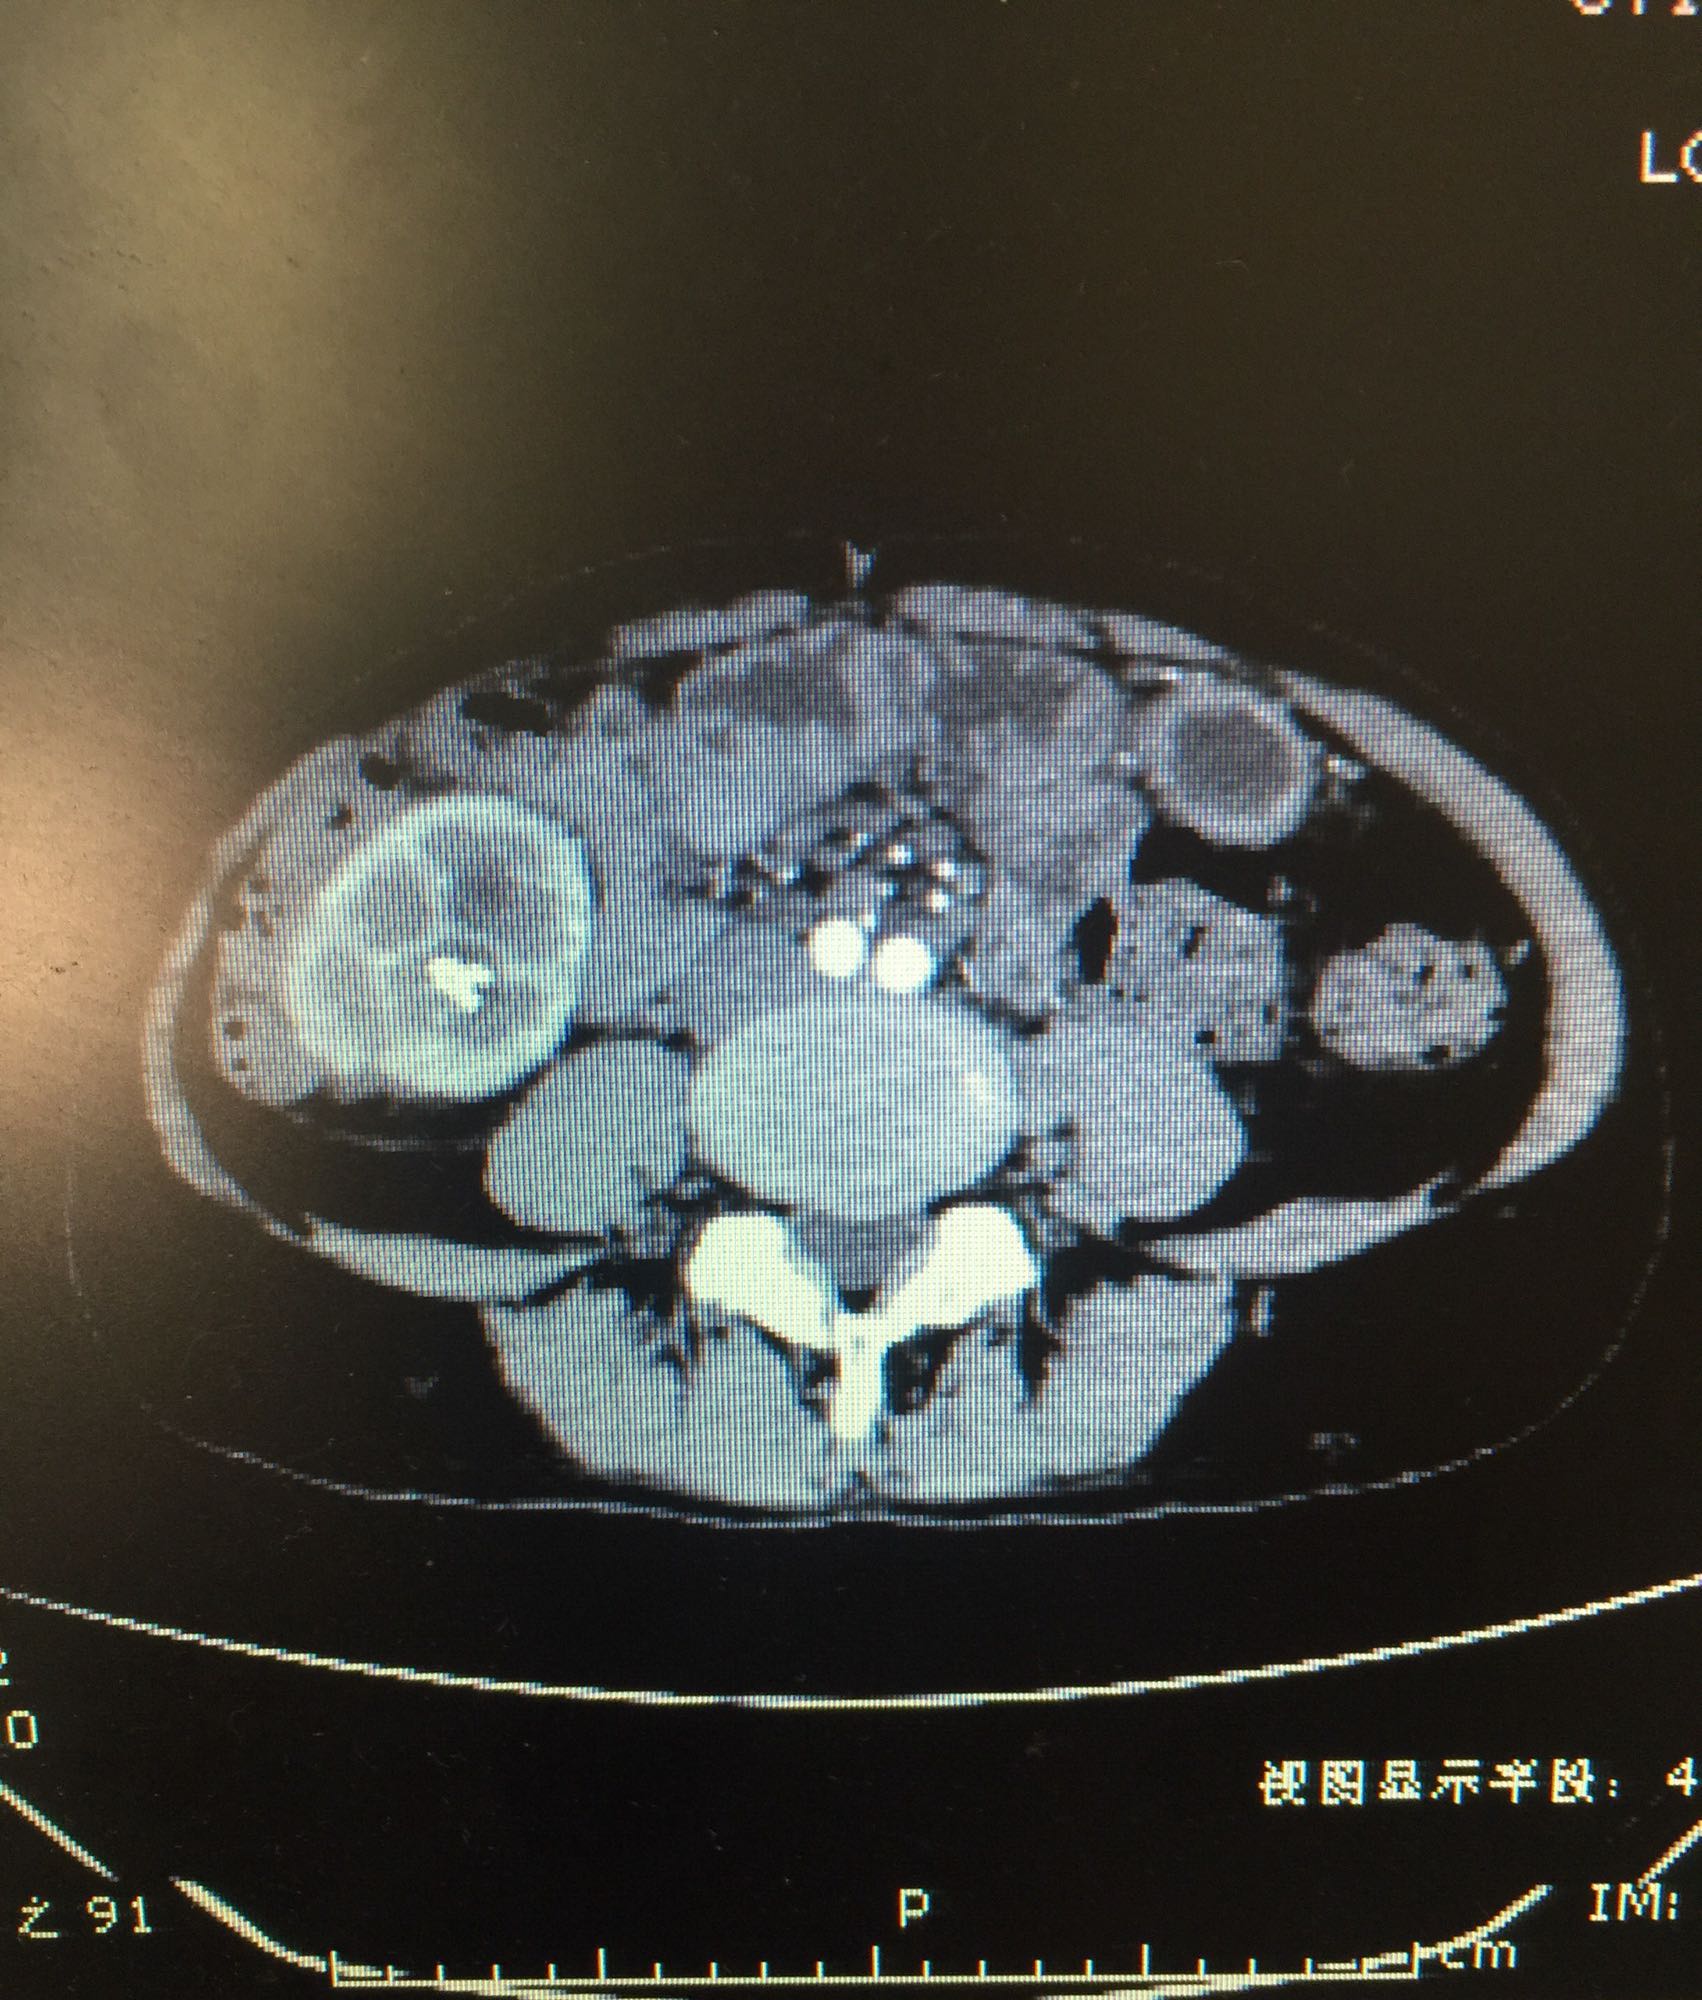

右侧肾脏巨大铸型结石一例

肾盂积水伴输尿管肾盂连接处梗阻 肾结石

右侧肾脏巨大铸型结石,右肾盂输尿管连接部狭窄? 拟完善GFR测定后决定下一步治疗方案,目前倾向于开放手术。

该患者结石大,且负荷大部分位于肾盂,肾盂几乎被填满,所以考虑是否有右侧输尿管肾盂连接部狭窄可能,结石负荷大,结合上述情况可行开放手术,一期整形 。 但若为UPJO,患者肾脏积水轻,肾脏皮质厚,肾功影响小,可能性相对小。行PCN结合超声吸附,一期清理肾盂内结石应该问题不大。 对于该患者的治疗,不知大家意见如何?